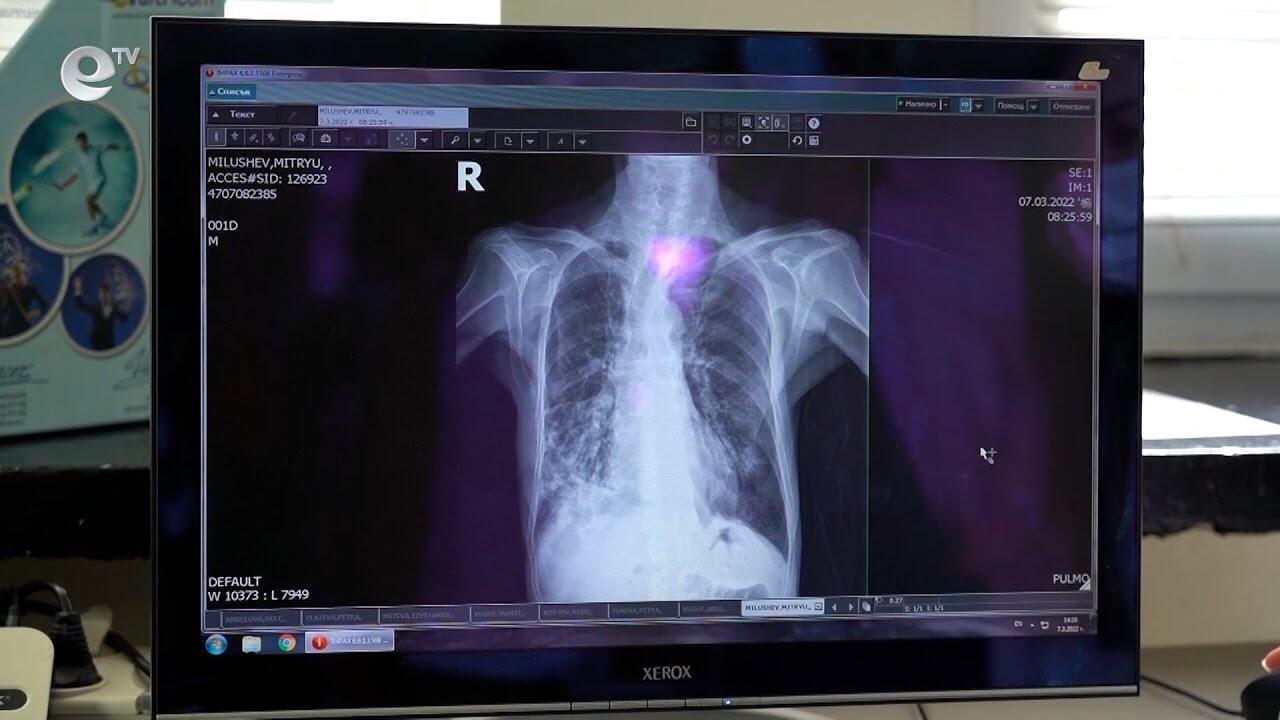

Едва 21 души се възползваха от безплатните прегледи за туберкулоза в Кърджали

Слаб интерес към Дните на отворени врати за превенция на туберкулозата отчетоха в Кърджали. Кампанията се проведе през изминалата седмица в многопрофилната болница.